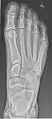

Extremities

A projectional radiograph of an extremity confers an effective dose of approximately 0.001 mSv, comparable to a background radiation equivalent time of 3 hours.[16]

The standard projection protocols in the UK are:[15]

• Hand - DP and Oblique

• Fingers - DP and Lateral

• Thumb - AP and Lateral

• Femur - AP and Lateral

• Knee - AP and Lateral. Intra Condular projections on request

• Patella - Skyline projection

• Tibia and Fibula - AP and Lateral

• Ankle - AP/Mortice and Lateral

• Calcaneum - Axial and Lateral

• Foot / Toes - Dorsoplantar, Oblique and Lateral.[19]